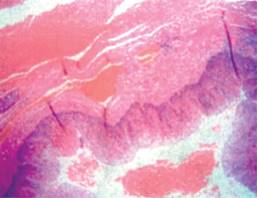

La paciente tuvo evolución satisfactoria, iniciando vía oral a las 48 horas del postoperatorio y siendo egresada a las 72 horas, la dieta postoperatoria se manejó de manera progresiva de líquidos a papilla, posterior blanda y picados finos, para finalmente continuar con dieta completa. Patología reporta la pieza como divertículo verdadero (Figura 5). En el seguimiento por consulta externa con adecuada evolución, tolera la dieta y no presenta sintomatología de reflujo gastroesofágico.